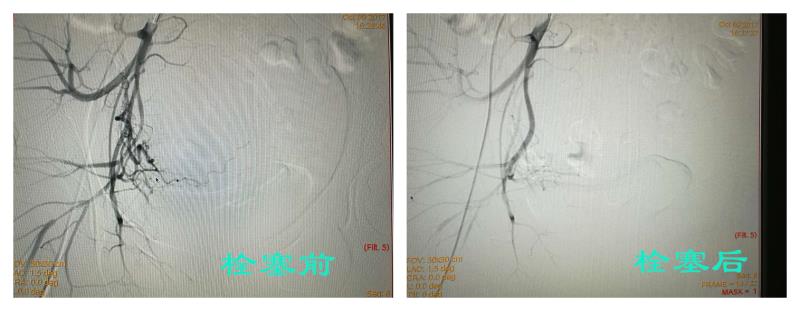

10月9日,介入科为李女士实施了子宫动脉栓塞术, 10月11日,妇科为患者实施了宫腔镜下清宫术+腹腔镜下子宫瘢痕切除并子宫修补术。在介入科与妇科的共同努力下,成功地保留了患者子宫,术中子宫出血仅200ml。

据巴彦淖尔市医院介入科主任张辉介绍,子宫动脉栓塞术系采用超选择性子宫动脉插管栓塞,阻断供血血管,防止出血,减轻或消除病症,从而达到治疗目的。该术式具有创伤小、快速止血、安全高效等优点,可有效控制阴道大出血,降低子宫切除风险。